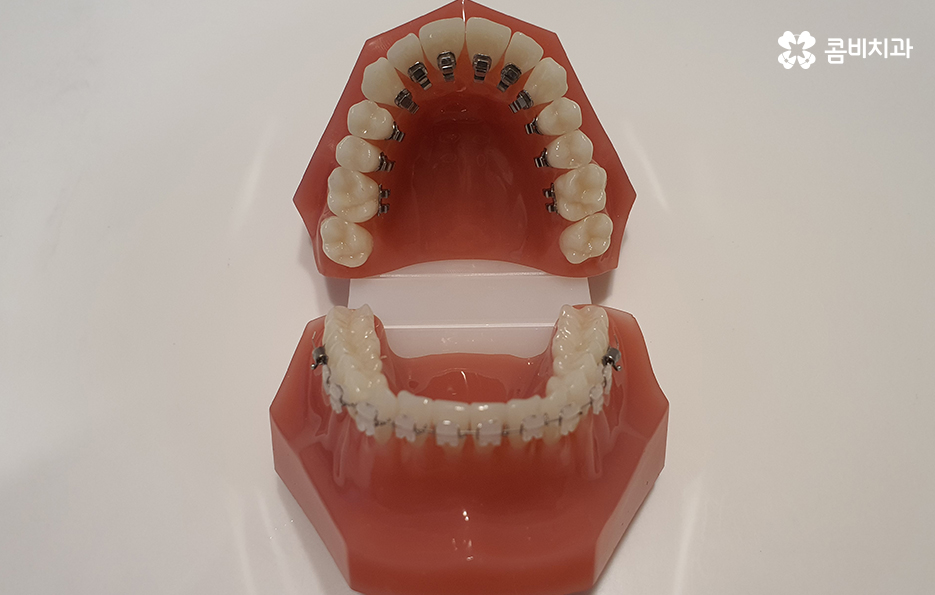

평상시 대화를 하고 웃을 때 주로 보이는 치아는

윗니인데 치아교정을 할 때 윗니는

치아의 안쪽에 장치를 부착하고

아랫니는 치아의 바깥쪽에 장치를 부착하는

방식을 콤비교정이라고 합니다.

치아의 안쪽에 장치를 부착하여 시술이 진행되는 방식을

설측교정이라고 하는데 콤비교정은 윗니는 설측,

아랫니는 순측으로 시술이 진행된다는 특징이 있습니다.

장치를 부착하고 치료의 경과 모습

윗니가 설측으로 시술이 진행되고 있는 모습이며